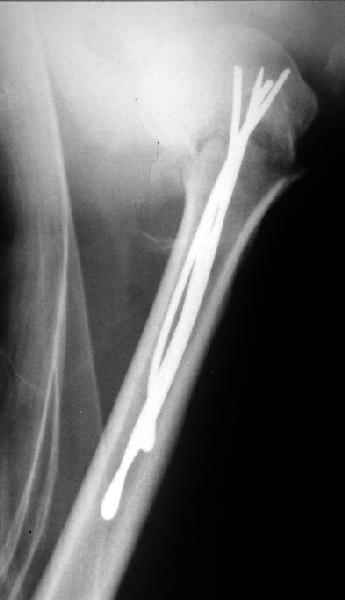

Спасибо за участие в дискуссии -перелом шейки плеча, для себя я прояснил многие технические моменты...

Посылаю послеоперационные Рг граммы.

Поздравляю, получилось просто замечательно. Если можно, расскажи чуть подробнее, как делали - как вправляли, как вводили спицы, поворачивали ли их?

Спасибо за поздравления:-))

Я и сам доволен результатом. В предпоследнем письме я кратко описал ход операции - закрыто репонировать не удалось( 2 недели с момента травмы и 1 неделя после неудачной репозиции) после удаления пучков спиц, пришлось сделать - 2см разрез на уровне перелома и с помощью периостального элеватора (золотое правило механики) *одеть* головку на дистальный отломок.

Спицы проводил через старые отверстия, вращая пучок импактором- направителем при его введении в головку.